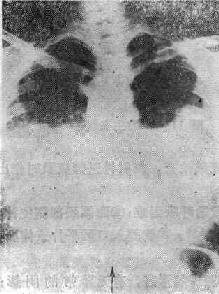

第一节 肺水肿的X线表现放射诊断专家根据液体在肺内积聚的部位,将肺水肿分为间质性肺水肿和肺泡性肺水肿,根据肺水肿发生发展的过程分为急性或慢性肺水肿。 一、肺泡性肺水肿 液体积聚在肺的终末气腔内。心源性或非心源性致病原因,引起肺腺泡内液体的积聚,表现为肺泡的实变。小者呈腺胞结节状阴影,融合扩大呈斑片状,可单侧或双侧分布。但以双侧分布为多见。根据分布和形态可分为三种类型。 (一)中央型肺水肿 以两肺门为中心向两肺野扩展的阴影(可见支气管气影征),由深变淡,肺野边缘、肺尖和肺底清晰,呈“蝶翼状”分布,这是中央型肺水肿典型的X线表现(图114-1)。常见于心脏和尿毒症患者。治疗及时一般很快吸收消失(3天之内);如治疗不及时,肺泡内除渗液外,可以为凝固的纤维蛋白和巨噬细胞所充填。可产生炎性改变。肺水肿可继发感染。

图114-1 心源性肺水肿的X线表现 (二)弥漫性肺水肿 呈弥散性分布于两肺野,其大小和密度不等,轮廓不清,可融合而呈斑片状阴影。以非心源性,如成人急性呼吸窘迫综合征(ARDS)为多见。 (三)局限型肺水肿 肺泡性肺水肿所产生的阴影可呈局限性,以右侧多见。这可能与心脏病患者喜欢右侧卧位,和心脏增大压迫左肺动脉,使左、右肺血液量不同所致。 二、间质性肺水肿 液体积聚在肺间质内。以现出间隔线为特征。 (一)肺纹理增强,肺血再分布 即上肺野血管纹理增多,而下肺野血管纹理减少。 (二)肺门阴影增大而且轮廓不清。 (三)可见KerleyA、B、C、D线以A、B线常见,KerleyB线多见于两肺下野肋膈角区,呈横行与胸膜垂直的短线状影。KeleyA线较B线少见,多出现于中央区,较B线长,可呈弧形或弯曲状,斜行向肺门。 (四)其他表现 如心呈二尖瓣型增大,少量胸腔积液,肺静脉增高的表现等。